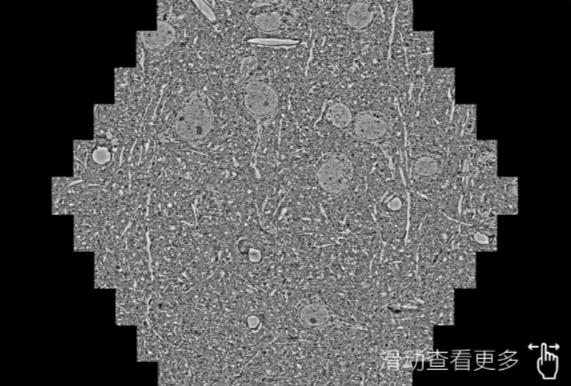

鼠脑切片。左图使用吐鲁番蔡司吐鲁番扫描电镜MultiSEM706对165μmx143pm面积区域成像,耗时仅需1.5秒。右图为鼠脑切片中30μm区域放大效果。样品由芝加哥大学B.Kasthuri提供。

使用蔡司高速吐鲁番扫描电镜MultiSEM对1mm²人脑皮层组织进行高分辨成像,并对其中的各种细胞结构进行三维重构分析。左图展示了2x3mm²组织平面中锥体神经元的三维重构效果。右图显示了局部体积神经元三维重构。图像由哈佛大学chtman实验室提供,渲染图由D. Berger 制作。